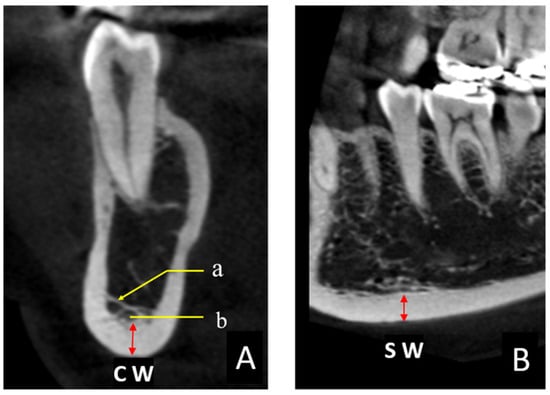

The thickness of the mandibular inferior cortical bone was measured in all CBCT images. These measurements were performed in two cross sections to obtain the coronal width (CW) and sagittal width (SW) twice on each side in 0.1 mm increments by one examiner (K.S.), using the image analysis software described above (Figure 2A,B). The target area was immediately below the mental foramen (area indicated as red arrow in Figure 2A,B), and the Hounsfield unit (HU) display tool provided with the software was used as an indicator to digitally measure the bone tissues with a value of ≥1000 [22]. The HU value could be easily displayed on the viewer image by manipulating the pointer in any region. Finally, the CW and SW values were averaged to obtain the mandibular cortical width (MCW). When the CBCT imaging site was the whole jaw, two sites were measured (one on the left and one on the right), and when the imaging site was only one side, one site was measured. In some cases, the bone margin immediately below the mental foramen was not included in the imaging area, in which case an adjacent area, such as that immediately below the first molar, was measured.

Figure 2. (A) CBCT coronal section of a C2 (Figure 1B) case. (a) Trabecular structures running buccolingually. (b) Areas with small virtual HU values (578) were not included in the measurement, and areas with HU values of >1000 (red arrows) were measured to obtain the coronal width (CW). (B) Sagittal section of the same region. The sagittal width (SW) was measured along with the CW, and the mean value of the CW and SW was defined as the mandibular cortical width.